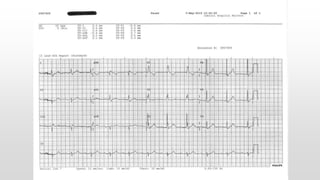

This document discusses various cases of collapse and syncope. It defines collapse as transient loss of consciousness with loss of postural tone and full recovery. Syncope is defined as loss of postural tone with or without loss of consciousness and full recovery. It then discusses the multiple potential causes of collapse and syncope including toxicological, cardiac conduction abnormalities, structural cardiac issues, autonomic dysfunction and more. It then goes through 9 case examples, discussing important questions to ask, potential tests and interventions for each case.